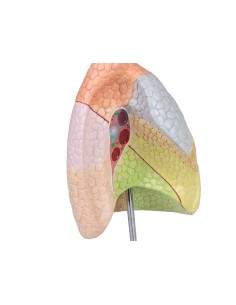

Découvrez le monde de l'anatomie avec des modèles anatomiques de précision

Bienvenue sur Tuttoanatomia.it, le portail de référence en Italie pour l'achat de modèles anatomiques, de posters, de lits portables, de simulateurs médicaux et de littérature spécialisée. Grâce à nos modèles anatomiques de pointe de 3B Scientific et Erler Zimmer, nous offrons une expérience d'apprentissage inégalée.

Des modèles anatomiques détaillés pour tous les besoins

Du crâne en 22 parties à verrouillage magnétique aux modèles de colonne vertébrale, des modèles d'articulation aux modèles de cœur, chaque pièce de notre collection est conçue pour une immersion totale dans l'étude de l'anatomie humaine. Nos modèles, réalisés à partir de scans d'os réels, garantissent une expérience tactile authentique et une fidélité de poids presque identique aux originaux.

Des outils pédagogiques innovants pour l'enseignement et la pratique de la médecine

Indispensables aux étudiants comme aux professionnels, nos modèles anatomiques sont des outils pédagogiques qui permettent d'observer les structures anatomiques avec précision, en évitant les dissections ou les études invasives. Ils sont également utiles pour expliquer les pathologies aux patients, ce qui rend la communication plus efficace et permet de gagner un temps précieux.